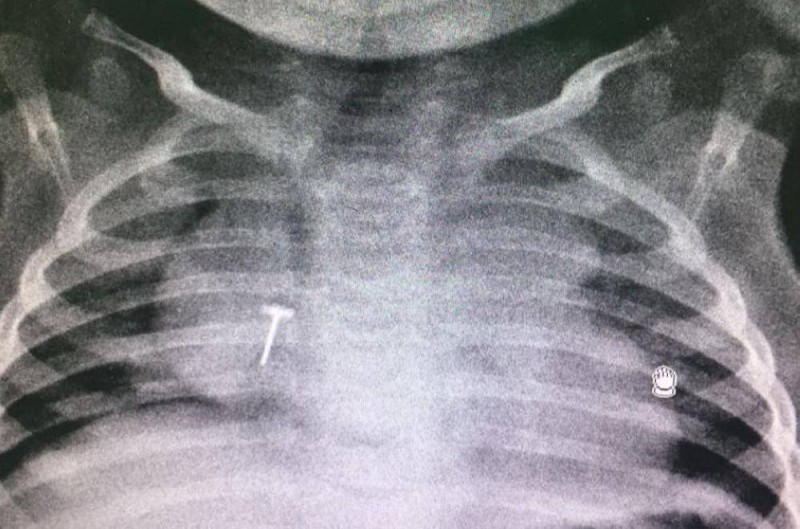

وأوضح رئيس طوارئ مستشفى الأطفال بالمدينة الدكتور فيصل الروقي، أن ابتلاع الأجسام الغريبة يعتبر مشكلة كبيرة، خصوصا في فئة الأطفال من عمر 6 أشهر إلى 3 سنوات، حيث قد تسبب بعض حالات بلع الأجسام الغريبة حالات اختناق ووفاة في بعض الأحيان، مبيناً أن ابتلاعها يعرف بدخول أي جسم غريب لمجرى التنفس أو مجرى الطعام من قِبَل الأطفال من قصد أو من غير قصد، مثل: قطع البلاستيك، قطعة معدنية، بلع بطارية، بلع بالون، الأزرار، الدبابيس، عظام السمك، القطع النقدية.

وأضاف: «تعتمد طرق علاج حالات ابتلاع الأجسام الغريبة عند الأطفال على حالة المصاب، فالتدخل أمر ضروري، ويكون ذلك في بث الطمأنينة للمصاب وإرشاده لإزالة الجسم الغريب مع مراعاة عدم الضغط على البطن، أو إذا فقد المصاب القدرة على الكلام، أو الصراخ، أو فقد الوعي فمن الضروري التدخل الطبي الفوري لمتابعة حالته الصحية وإجراء التصوير الطبي والتدخل الجراحي اللازم إن استدعى الأمر».